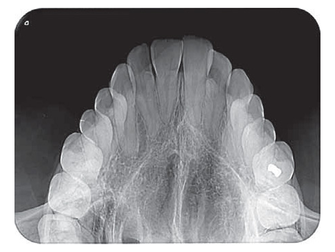

La tecnología PCS del VistaScan Mini reproduce lesiones de caries D1 e instrumentos de endodoncia hasta ISO 06 de forma fiable. 22 LP/mm y 16 bit (65 536).

El reconocimiento del detalle de 22 LP/mm de las placas radiográficas VistaScan ofrece una resolución de imagen mejor que la de la película radiográfica y, por consiguiente, mejor que la de la competencia. La tecnología Photon Collecting System (PCS) de Dürr Dental está más desarrollada que las placas radiográficas.

¿Cambiar la película radiográfica por la placa radiográfica “digital“? . El procedimiento radiográfico sigue siendo el mismo. Pero la seguridad diagnóstica es mayor gracias a un reconocimiento de los detalles óptimo y a un elaborado software de apoyo. Con el VistaScan Mini se beneficiará de las ventajas de la tecnología de placas radiográficas de Dürr Dental en el formato más compacto. Las placas radiográficas finas y flexibles son cómodas para el paciente y su revestimiento especial las hace especialmente duraderas.